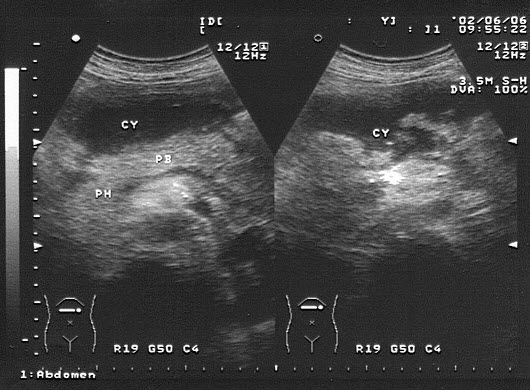

2、单项选择题

下图为宫内孕囊声像图,可见心管搏动,该胎儿至少大于多少周()

A.6周

B.9周

C.10周

D.12周

E.8周